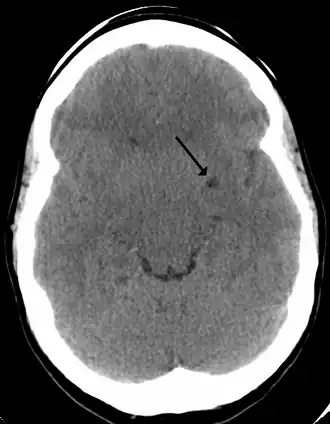

![]() A perivascular space as seen on CT | |

In humans, perivascular spaces surround arteries and veins can usually be seen as areas of dilatation on MRI images. While many normal brains will show a few dilated spaces, an increase in these spaces may correlate with the incidence of several neurodegenerative diseases, making the spaces a topic of research.[4]

Perivascular spaces may be enlarged to a diameter of five millimeters in healthy humans and do not imply disease. When enlarged, they can disrupt the function of the brain regions into which they project.[5] Dilation can occur on one or both sides of the brain.[7]

Dilated perivascular spaces are categorized into three types:[7]

- Type 1 are located on the lenticulostriate arteries projecting into the basal ganglia

Perivascular spaces are most commonly located in the basal ganglia and white matter of the cerebrum, and along the optic tract.[13] The ideal method used to visualize perivascular spaces is T2-weighted MRI. The MR images of other neurological disorders can be similar to those of the dilated spaces. These disorders are:[7]

Perivascular spaces are distinguished on an MRI by several key features. The spaces appear as distinct round or oval entities with a signal intensity visually equivalent to that of cerebrospinal fluid in the subarachnoid space.[7][14][15] In addition, a perivascular space has no mass effect and is located along the blood vessel around which it forms.[14]

The clinical significance of perivascular spaces comes primarily from their tendency to dilate. The importance of dilation is hypothesized to be based on changes in shape rather than size.[13] Enlarged spaces have been observed most commonly in the basal ganglia, specifically on the lenticulostriate arteries. They have also been observed along the paramedial mesencephalothalamic artery and the substantia nigra in the mesencephalon, the brain region below the insula, the dentate nucleus in the cerebellum, and the corpus callosum, as well as the brain region directly above it, the cingulate gyrus.[5] Upon the clinical application of MRI, it was shown in several studies that perivascular space dilation and lacunar strokes are the most commonly observed histological correlates of signaling abnormalities.[13]